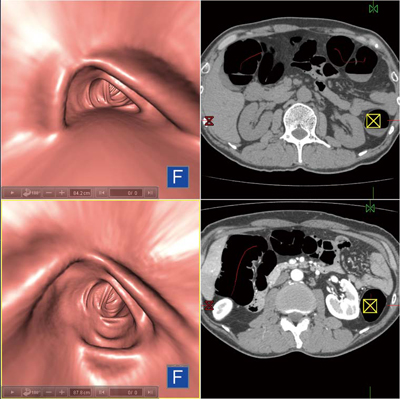

また,2体位表示は,体位により経常の変化するポリープ病変の観察や残渣の移動確認も有用である。以下に,2体位表示機能の使用例を示す。仰臥位画像で観察を進めていくと,残液により視覚が確保されない部分が現れた。ここで比較画面に切り替えると,腹臥位画像が仰臥位の位置に合わせて表示される。視点位置を連動させて観察を行うことで,仰臥位では残液に隠れていた部分の情報が腹臥位画像より得られる(図7)。 |

図7 2体位表示

上段:仰臥位 下段:腹臥位 |